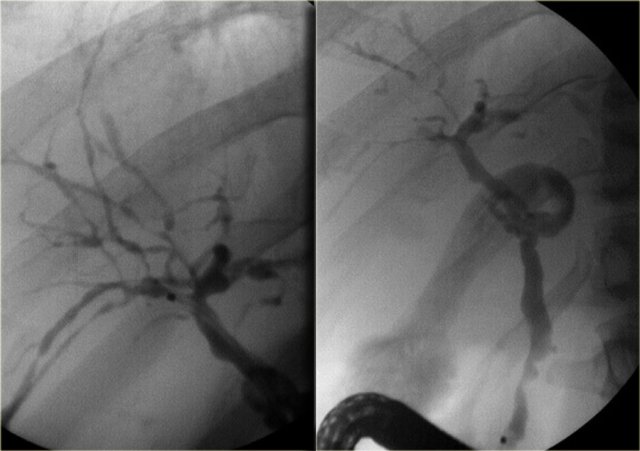

On the left we see images of a patient with Caroli disease.

Notice the intrahepatic duct dilatation and the normal caliber of the choledochal duct (extrahepatic bile duct).

The hallmark of Caroli disease is intrahepatic duct dilatation.

The dilatation can be very large and saccular as seen in the case on the left or it can be very linear.

On the left we see a dot within the dilated ducts.

When we put on the color doppler, we will notice that these structures contain blood flow and represent portal veins.